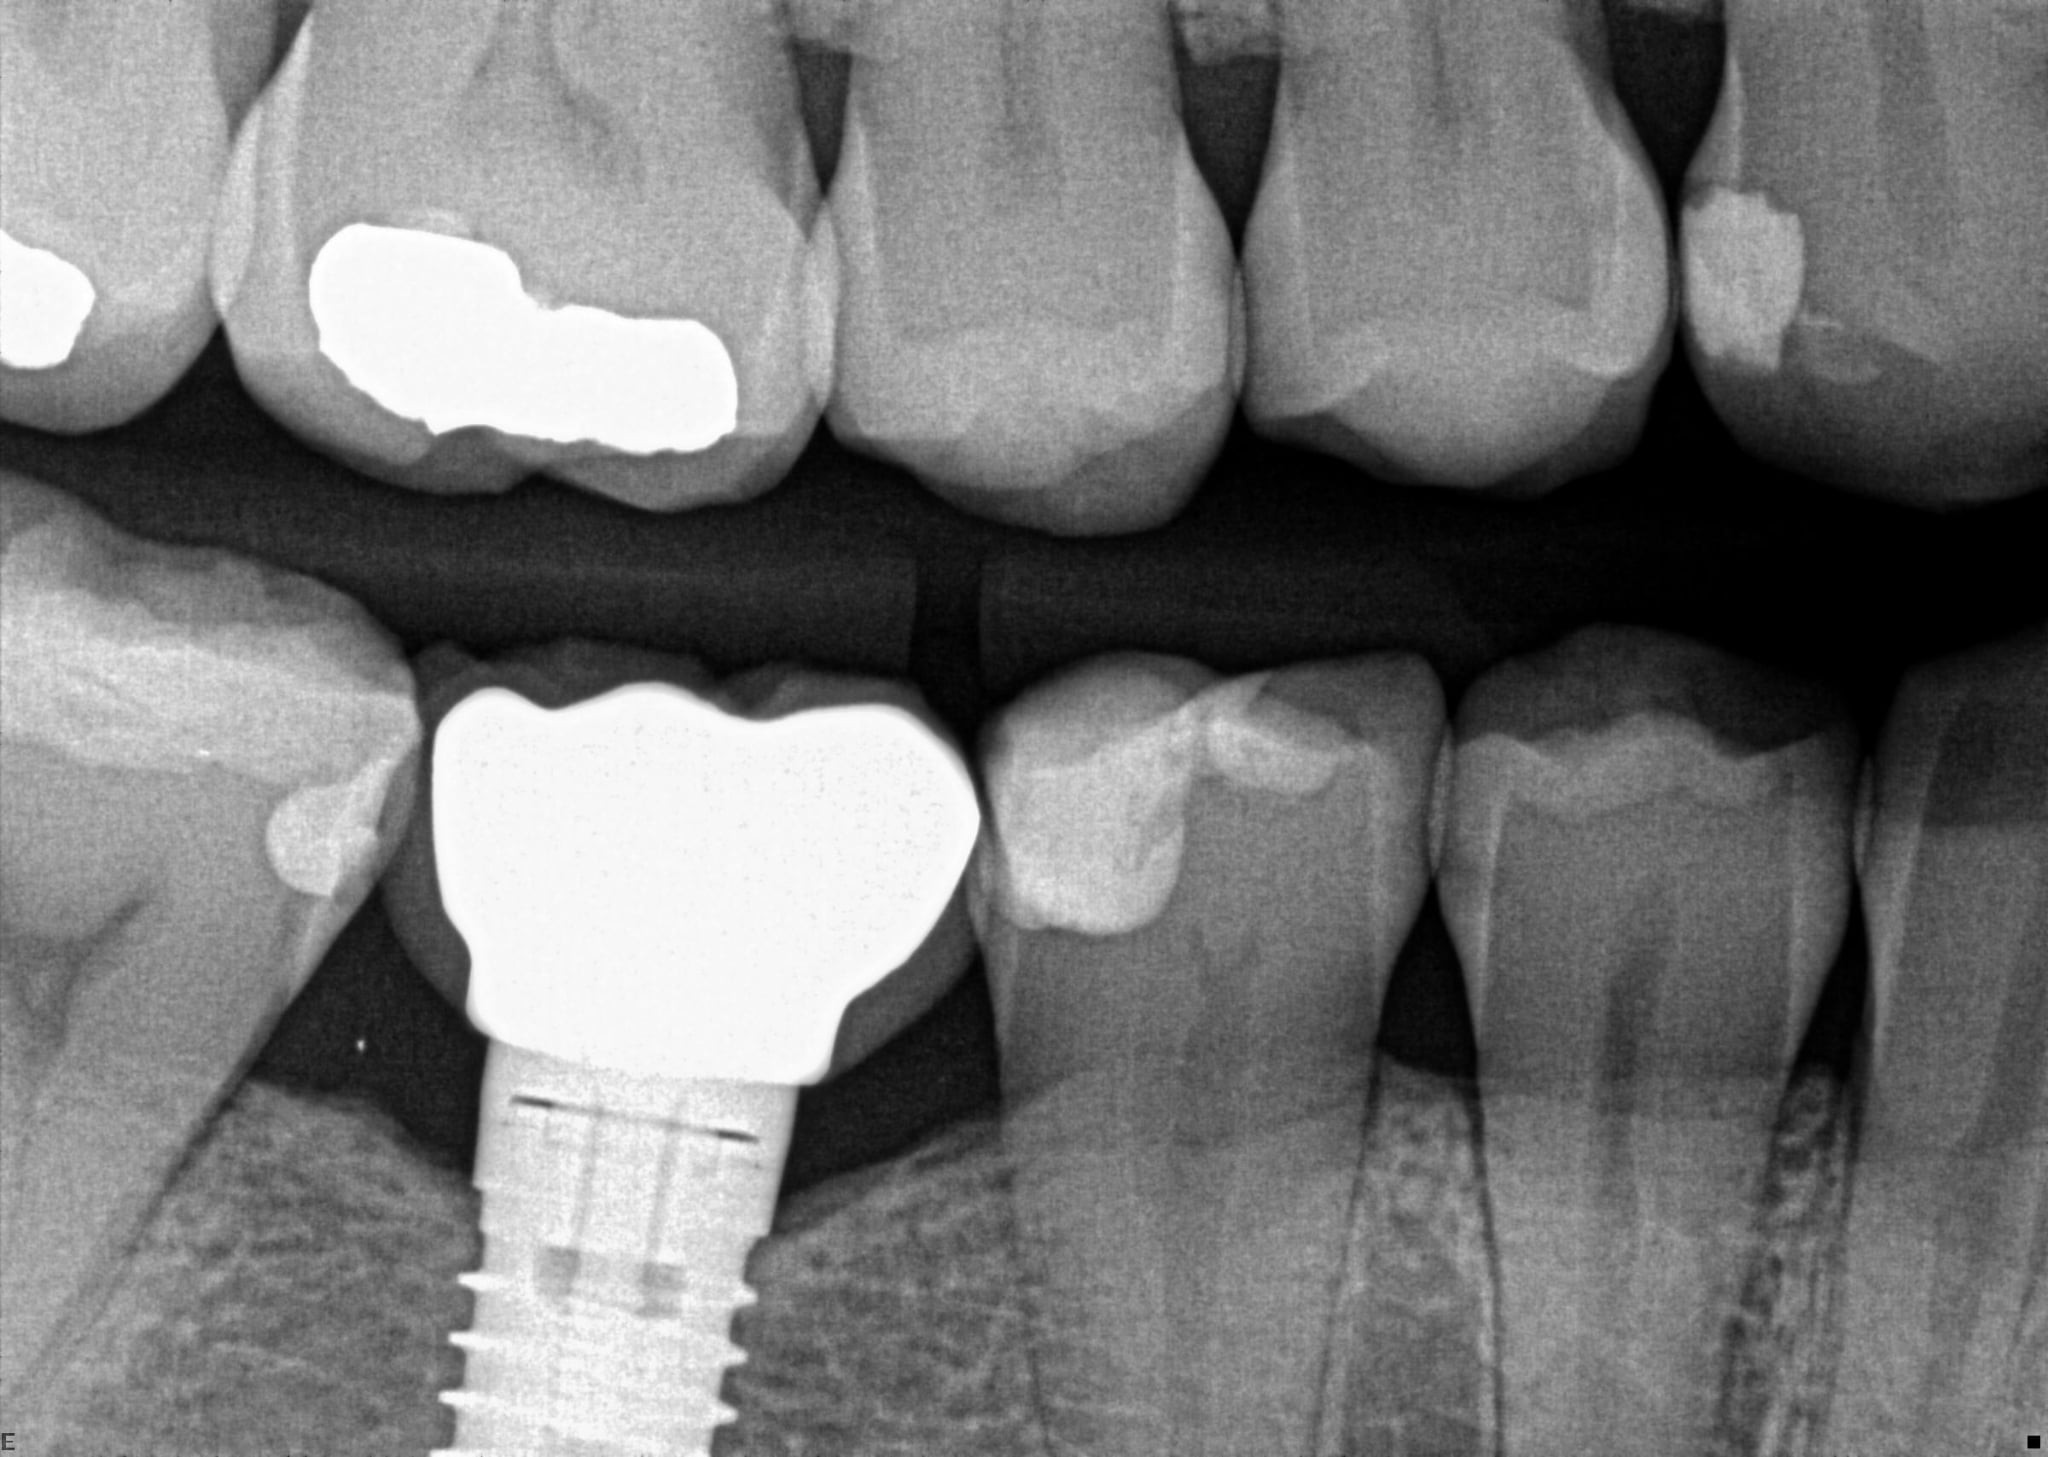

2. In the X ray bellow for which jaw periodontal bone loss is evident?